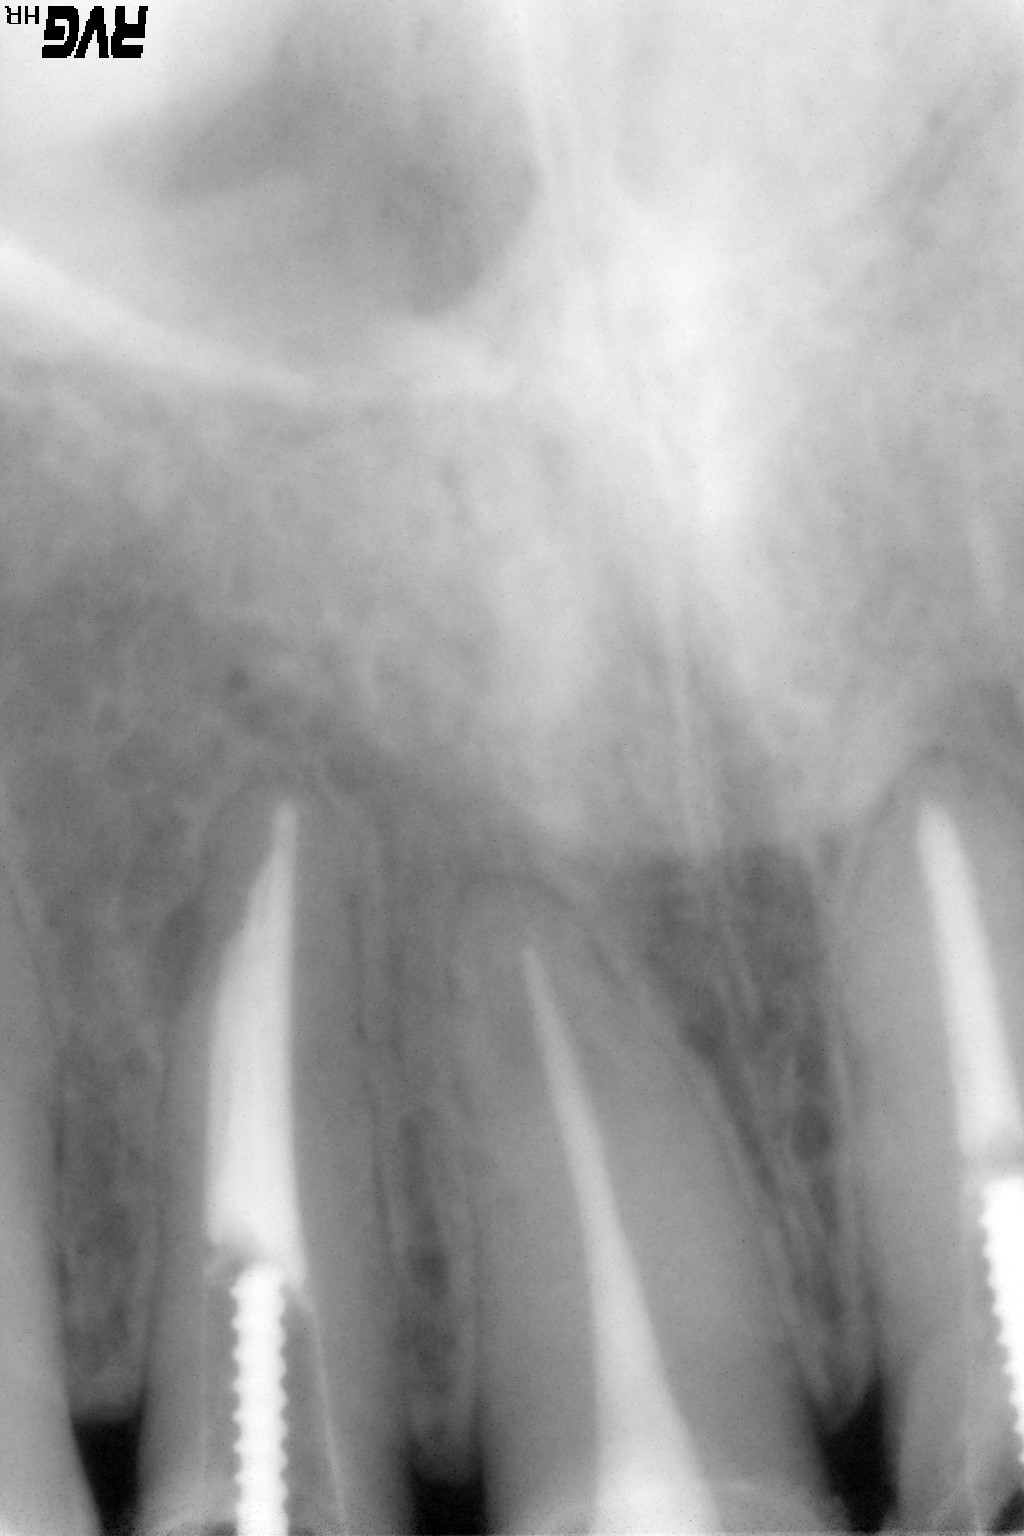

右上前歯に違和感があるとの主訴で来院。デジタルX線写真撮影により右上2番の根尖部遠心に透過像が認められた。感染根管治療を行い、根充後違和感は消失。術後のレントゲンは7年後に撮影したものであるが、透過像は消失している。